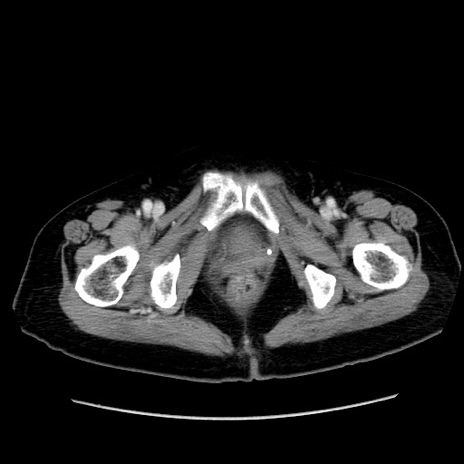

冠状断像

【症例】80歳代女性

【主訴】下腹部痛

【現病歴】約8時間前より下腹部痛の出現あり、救急外来受診。

【既往歴】両側付属器切除

【身体所見】意識清明、下腹部正中に手術痕あり、その部位に一致して圧痛と反跳痛あり。腸蠕動音は亢進。

【データ】WBC 9300、CRP 0.15